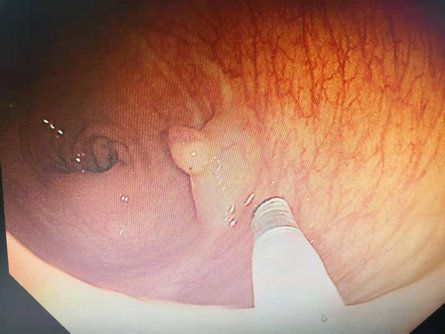

今年以来,我院消化内科积极开展新技术、新项目。5月25日,消化内科主任、副主任医师李红钊和科室内镜医师团队为68岁患者独立实施了内镜下粘膜切除术(EMR)。患者高某,女,以“慢性便秘”收住院。入院后行结肠镜检查提示:降结肠息肉,大小0.5cmx0.4cm,扁平状,(病理腺瘤样息肉)。直肠息肉,大小0.8cmx1.0cm,表面呈分叶状,有亚蒂(病理绒毛管状腺瘤)。在术前充分讨论的基础上,与患者及家属积极沟通同意后,给予降结肠息肉APC治疗术和直肠息肉EMR治疗术,术后完整病理提示:管状绒毛状腺瘤伴腺上皮轻一中度异型增生。此项技术目前在我院己完成3例,均康复出院,填补了我院消化内镜介入治疗新技术--内镜下粘膜切除术(EMR)治疗领域的技术空白。

随着内镜操作技术的改进和镜下治疗新技术的不断开发,消化道息肉治疗的技术越来越成熟,目前内镜下息肉切除方法有:高频电切除、微波、射频、氩离子激光等。内镜下消化道息肉切除治疗的意义在于可全瘤活检,明确息肉性质,治疗出血,切除癌前病变,预防癌的发生。与传统剖腹手术相比,内镜下治疗费用低、不需麻醉、损伤小、痛苦少、术后恢复快、并发症及死亡率低等优点,对年老体弱及婴幼儿也适用,目前已被广泛接受,替代剖腹手术成为消化道息肉治疗的首选方法。内镜下粘膜切除术(EMR)是指在内镜直视下将病变粘膜进行局部切除,该切除方法只涉及黏膜层及部分黏膜下层,不涉及固有肌层。此前,该项目多在三级医院开展,我院消化内科该技术的顺利开展,将为全县广大人民群众带来新的福音,也为我院消化内科技术提升寞定了新的基础。